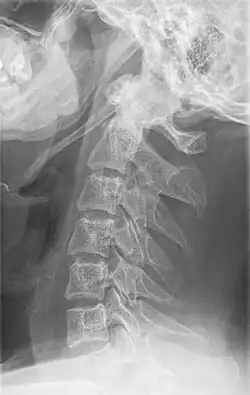

Radiograph, lateral view showing elongated stylohyoid process and stylohyoid ligament ossification -

Radiograph, lateral view showing joint-like formation in ossified stylohyoid ligament -